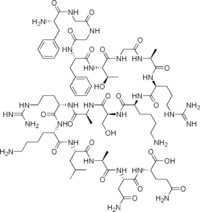

| Opioid peptides | Skeletal molecular images |

| Adrenorphin |  |

| Amidorphin |  |

| Casomorphin | |

| DADLE | |

| DAMGO |  |

| Dermorphin | |

| Endomorphin |  |

| Morphiceptin |  |

| Nociceptin |  |

| Octreotide |  |

| Opiorphin |  |

| TRIMU 5 |  |